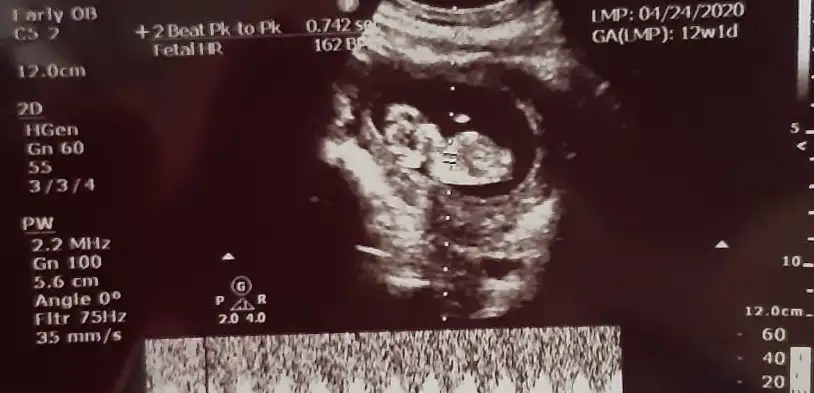

Kızlar tahminleri alalım nub prosu var dediler geldik.

Bildim ilk günden erkek dedim saglikla gelsinErkekmişşşş